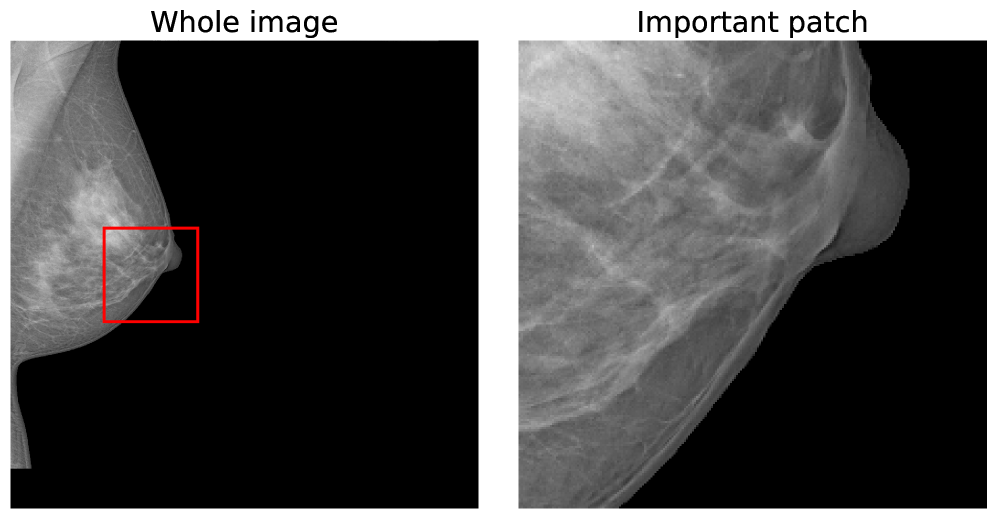

A further benefit of our approach is that the concept vectors can be used to gain an interpretable component about what the model is learning to look for. We can do this by showing example patches that correspond to the ’th concept vector activating and having the maximal response, i.e., making the classification determination. We provide an example for the first five concept classes on the BTMD dataset in Figure 4 and the RSNA-SMBC dataset in Figure 5. In both cases, the row corresponds to a concept, and 25 columns show 25 winning exemplars.

The BTMD dataset has considerably more visual variation in the images, making them more challenging to inspect as non-medical experts, but visual themes are generally discernible across each row in Figure 4. We note that there is no mechanism to force one concept vector to suppress other concept vectors for similar activations, and so we see some cross-pollination between the concept vectors. The RSNA dataset has less visual asperity, and visual patterns are more clearly observed in the rows of Figure 5.

Similarly, we can perform the same inspection for random iamges of the RSNA-SMBC dataset in Figure 10. Note that this dataset is not as obvious to non-medical professionals but each instance is a true-positive identification.